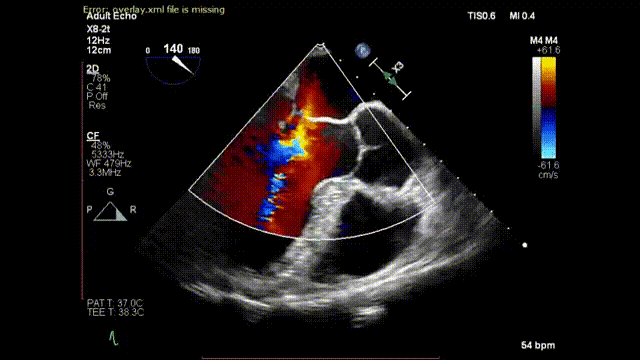

术后,患者二尖瓣反流立即消失,同时左房平均压明显改善。手术全程在超声引导下进行,操作可控,无放射线,心脏不停跳,无需体外循环,创伤小,不出血,恢复快。手术全过程充分体现了E-ChordTM安全、有效、微创、便捷的设计理念和以医生/患者为本的企业价值观。

术后二尖瓣反流消失

至此,E-ChordTM已在中山医院圆满完成三例手术。5月27日的首例患者及6月17日的第二例患者在植入人工腱索后,二尖瓣反流完全消失,术后随访结果理想。今天,完美完成的E-ChordTM治疗的第三例患者,再次验证了穿刺式腱索重建二尖瓣修复手术治疗二尖瓣反流的安全性和有效性。